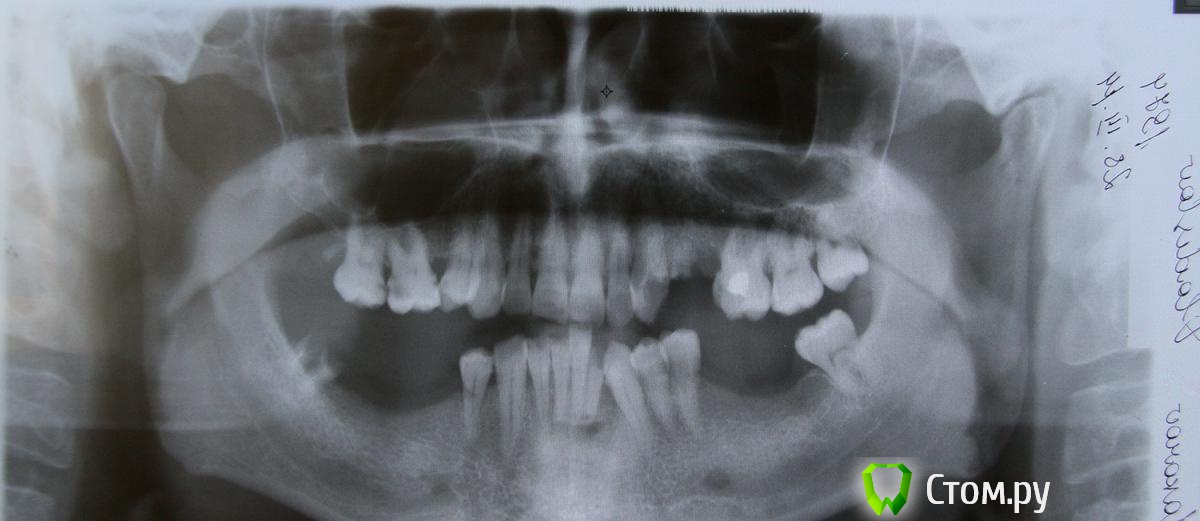

IvanK Опубликовано 9 апреля, 2014 Поделиться Опубликовано 9 апреля, 2014 удаление 18, 23?, 24,28, 48,32?проф гигиена + обучение,лечение у пародонтологасъемный протез/протезы кажется , что снимок перевернут.. Ссылка на комментарий

Военный Врач Опубликовано 9 апреля, 2014 Поделиться Опубликовано 9 апреля, 2014 удаление 18, 23?, 24,28, 48,32?проф гигиена + обучение,лечение у пародонтологасъемный протез/протезы кажется , что снимок перевернут..Можно добавить съемники акрил/акри-фри/нейлон/бюгель+мк Ссылка на комментарий